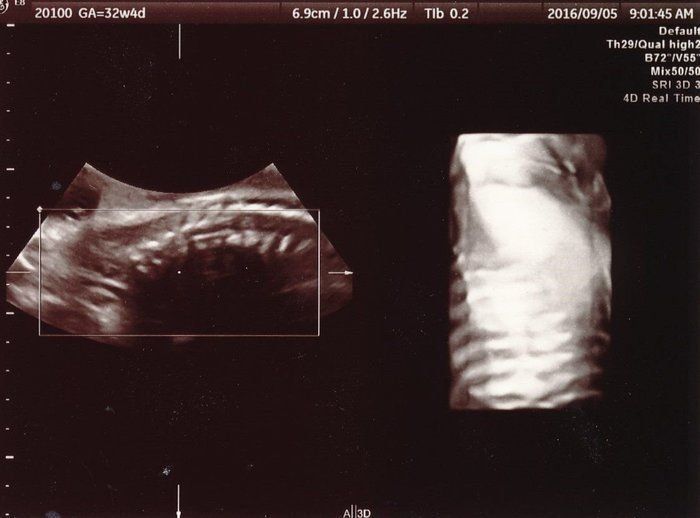

小吉さんの妊娠32週目のエコー写真

思いがけず授かった2人目は43歳の高齢出産!健診は不安と期待との板挟み!

赤ちゃんの背骨と肋骨がしっかりとできていることが確認できました。「小さいのにちゃんとあるな、頑張っているな」と感動したのを覚えています。